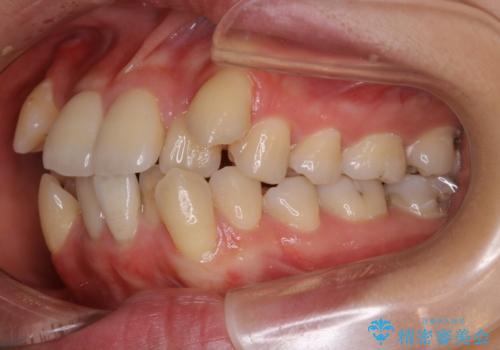

- 以前からコンプレックスだった八重歯の治療を主訴にご来院されました。

検査の結果、抜歯をすることでスペースを作って並べる方法が選択され、ワイヤー装置を用いた治療を開始することとなりました。

叢生の度合いが重く、抜歯が必要なケース。八重歯の部分以外には大きな問題は認められなかったため、劇的変化が起こる治療でも比較的短期間で終了することができました。